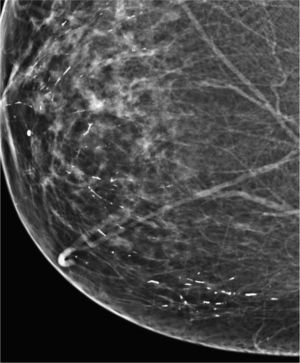

Las calcificaciones indeterminadas, como las demás, pueden ocupar una zona extensa de la mama (fig. 8), ser segmentarias (cuando ocupan un segmento) o estar agrupadas (fig. 9)6.